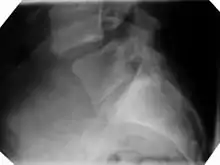

X-ray of the lateral lumbar spine with a grade III anterolisthesis at the L5-S1 level.

Degenerative spondylolisthesis at L5 - S1.

(B) Lateral radiograph pre-operative intervention.